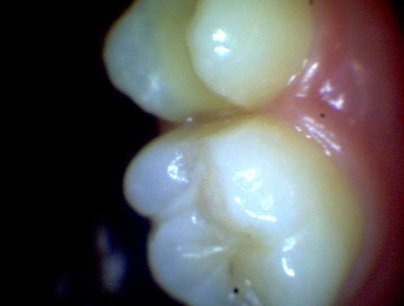

인레이 후에도 신경이 하얗게 보이는 모습